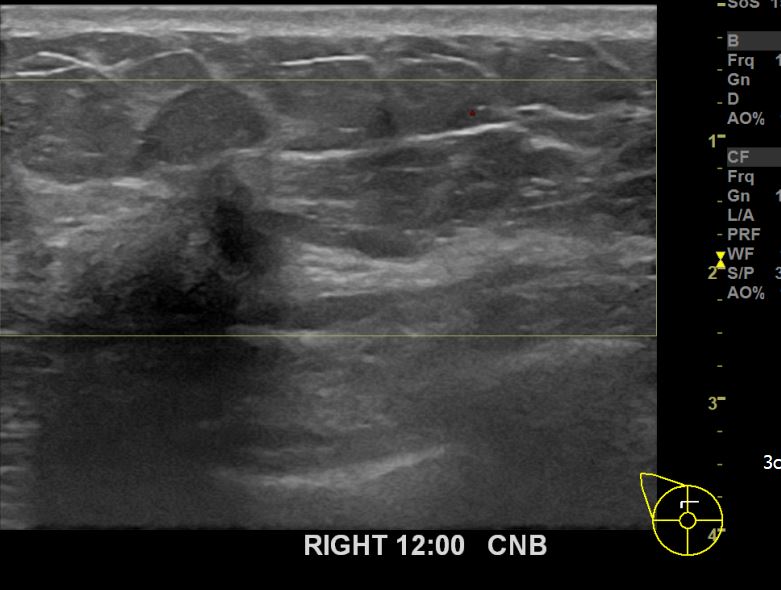

아산유외과개원후 661번째 유방암진단

상기환자 외부검사상 이상소견으로 내원하신 60대여성으로 우측에 의심스러운혹 조직검사시행해 유방암 진단되었습니다.